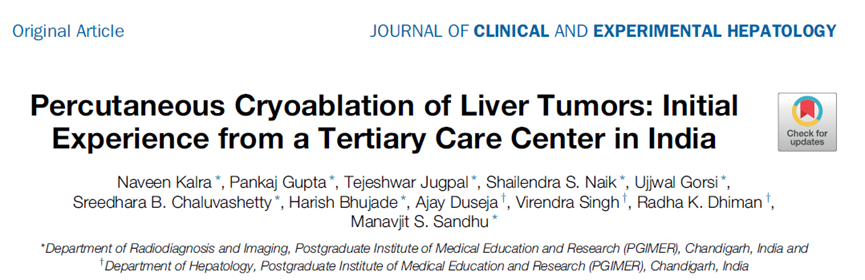

(9)直径> 5cm 的病灶,可通过多针穿刺和多点布针的方法尽可能适形、全面地消融病灶,也可根据情况行姑息性治疗,部分灭活肿瘤、减轻肿瘤负荷或延缓病情进展,以延长患者生存时间和提高生存质量。推荐方案是在消融后1 个月左右,复查动态增强CT 或MRI,或超声造影以评价消融效果,通过观察有无肿瘤残留,可分为完全消融及不完全消融。在肿瘤标志物检查中,原发性肝癌以血清甲胎蛋白水平作为评价指标,转移性肝癌多以癌胚抗原作为评价指标。治疗的不良反应主要有术后寒战发热、肝区疼痛、血清酶升高和血小板减少等,并发症包括感染、出血、胸腔积液、皮肤冻伤、肋间神经损伤、冷休克、胆瘘和肠瘘、肝功能衰竭等。充分术前准备、严格操作规范、准确定位与穿刺及术中动态监控是减少并发症发生率的重要方法。近年来,局部消融治疗得到广泛应用,其具有对肝功能影响少、创伤小、疗效确切、重复性好等特点。研究显示对于直径≤ 3cm 的肝细胞癌,局部消融与外科手术疗效无明显差异,冷冻消融使不适合手术切除的肝癌患者获得根治机会,现已是肝癌局部消融的常用方法。临床常见的原发性肝脏肿瘤是肝细胞癌,局部消融治疗现已是极早期和早期肝细胞癌患者治疗的一个组成部分。局部消融包括射频消融、微波消融和冷冻消融等。与其他方式相比,冷冻消融具有明显优点,包括影像监测冰球的边界、可激活有效的免疫效应、降低血管和其他关键结构损伤的发生率以及避免剧烈疼痛。本文探究了冷冻消融肝癌的临床有效性和安全性。回顾性纳入2018年10月至2019年8月期间接受冷冻消融手术的肝脏肿瘤患者9例, 5 名男性和 4 名女性。中位年龄为66 岁(范围:45-76 岁;平均年龄:62.4 岁)。其中7 例患者患有肝细胞癌,2 例患者患有肝转移癌。1例肝细胞癌患者有2个病灶,其余患者只有1个病灶。根据肿瘤位置,5个肿瘤位于胆囊附近,2个肿瘤位于右门静脉附近,2个肿瘤位于肝包膜附近,1个肿瘤位于胃附近。